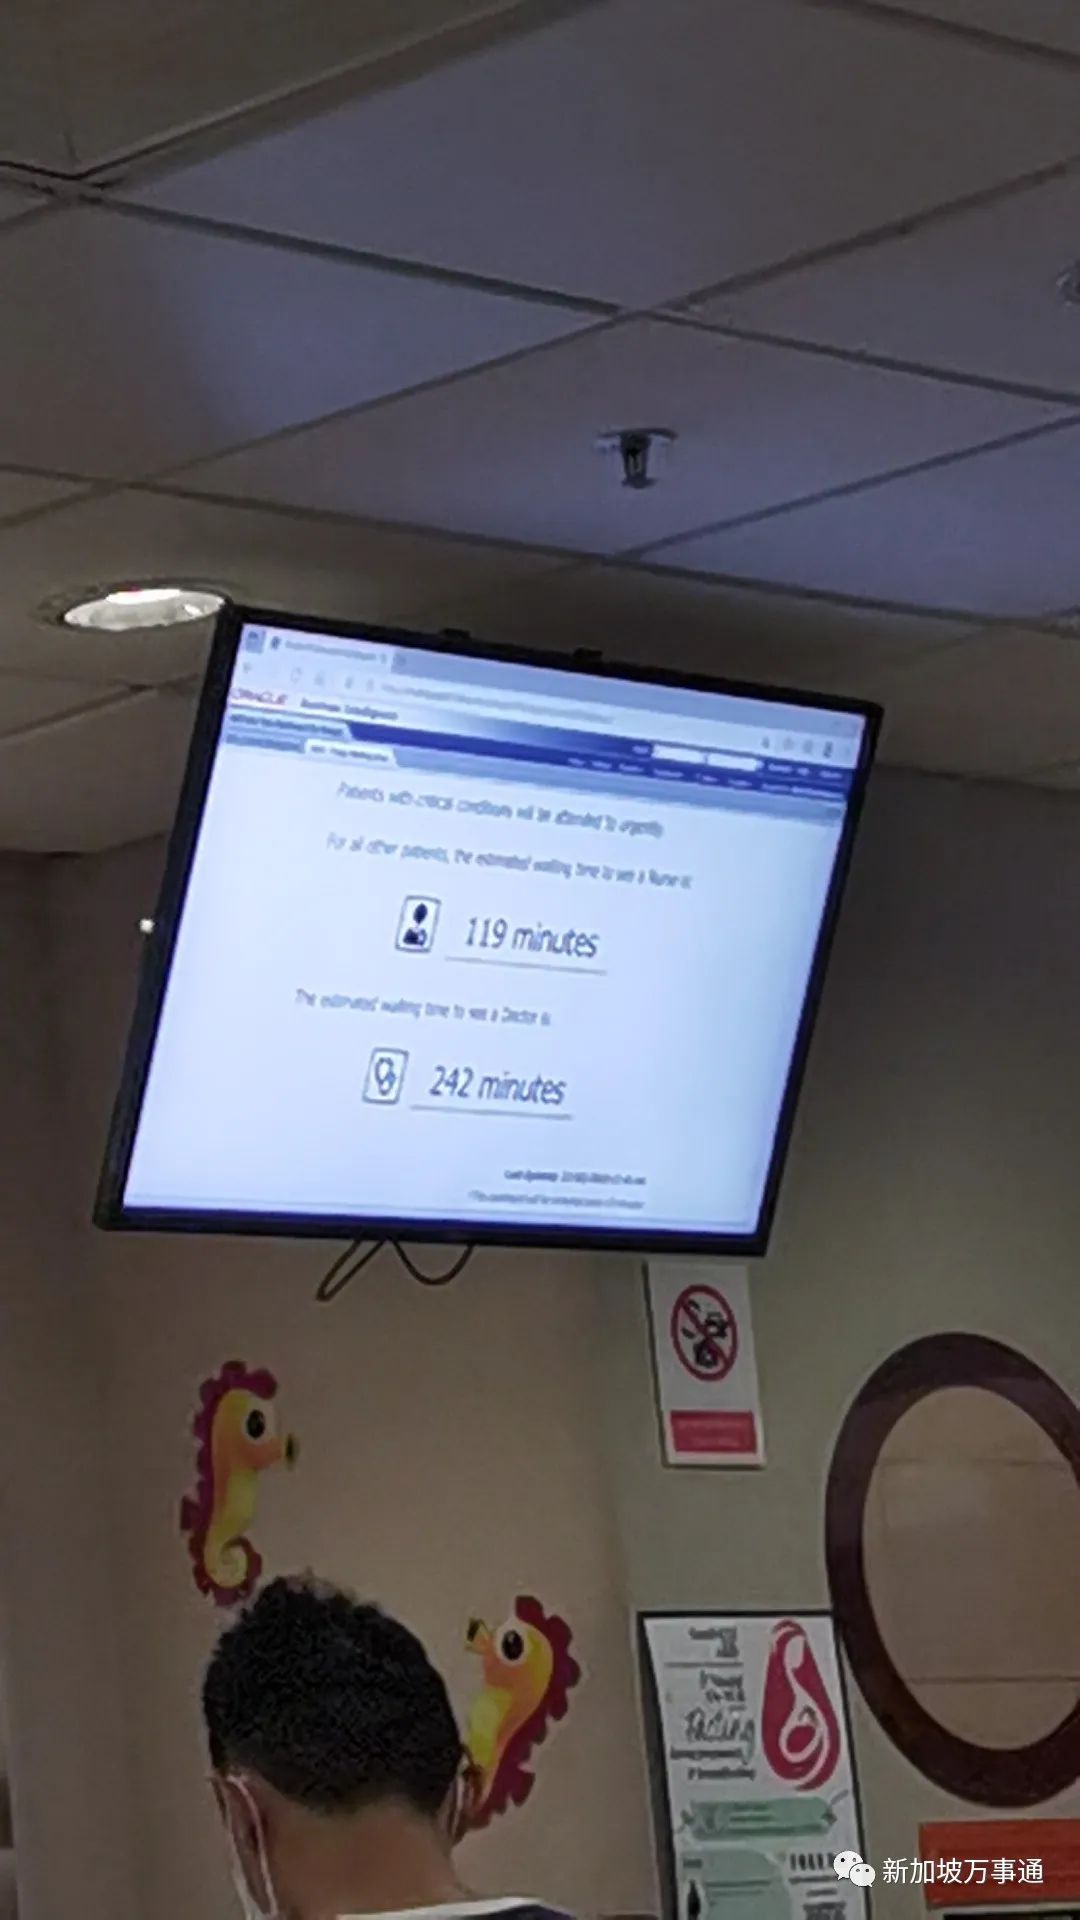

甲流导致多地医院人满为患